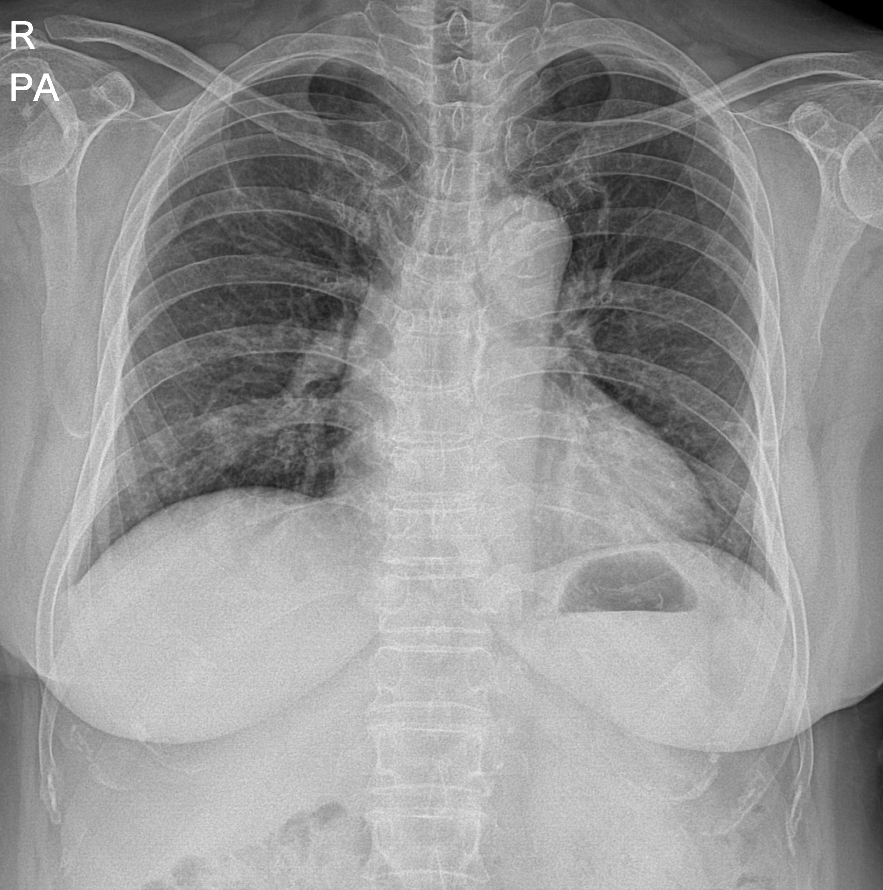

82세의 남자

왼쪽부터 폐렴 전 7개월 흉부 엑스레이, 진단 당시 좌상엽 폐렴